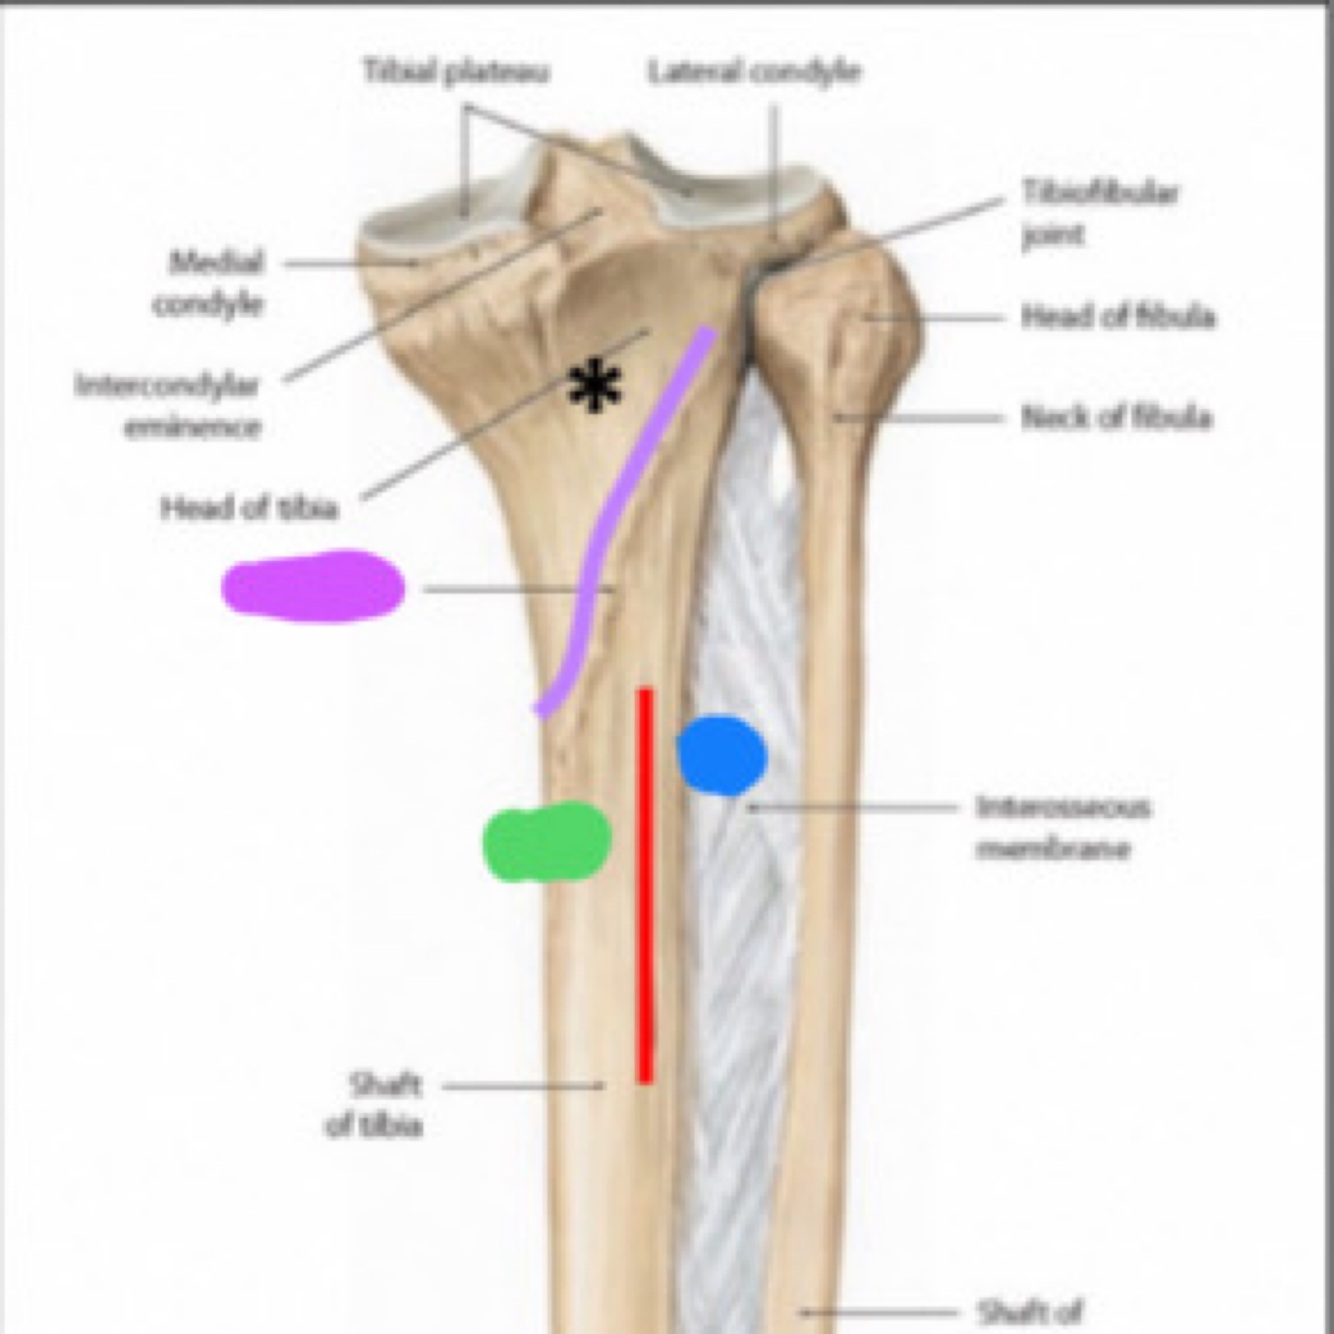

Quel est la structure que l’astérix pointe. Ya til une insertion musculaire a cet endroit? Laquelle?

A

La surface triangulaire du muscle poplité qui donne insertion du muscle poplité

La ________(rouge) sépare la diaphyse de la face postérieure du tibia pour 2 structures (bleu et vert).

Rouge: crête verticale

Vert: muscle long fléchisseur des orteils

Bleu: muscle tibial postérieur